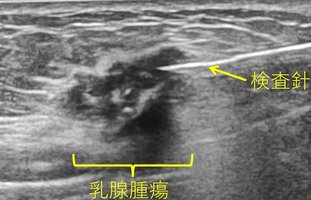

細胞診は、細い針を使って乳腺腫瘍から細胞を吸引し、顕微鏡で観察する方法です。この検査は局所麻酔が不要で、体への負担が少ないのが特徴ですが、採取できる細胞の量が少ないため、診断の確定が難しい場合があります。

針生検は、細胞診よりも太い針を使用して組織を採取する方法です。局所麻酔を使用し、多くの組織を採取できるため、診断の確実性が高まります。

マンモトーム生検は、専用の針を使用して機械で吸引をかけながら組織を採取する方法で、一度の穿刺(せんし)で複数の組織を採取することができます。この方法も局所麻酔が必要ですが、より多くの組織を採取できるため、腫瘍の詳細な情報を得ることができます。これらの病理検査は通常、超音波下で行われますが、超音波で判別が難しい小さな石灰化病変に対しては、エックス線を使用しながら行うステレオガイド下マンモトーム生検で組織を採取することができます。